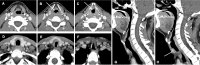

We present a case of multifocal laryngotracheal amyloidosis (LTA) in a 43-year-old man with persistent and progressive dysphonia and dyspnoea, and a first inconclusive histology. Although laryngeal amyloidosis accounts for fewer than 1% of all benign laryngeal tumours, it is in fact the most common site of amyloid deposition in the head, neck and respiratory tract. The clinical scenario is non-specific and diagnosis depends on a high degree of suspicion and on histology. Imaging is useful in mapping lesions, which are often more extensive than they appear during laryngoscopy. Despite being a benign entity, the prognosis is variable with a high-rate and long-latency recurrences, requiring long-term follow-up.